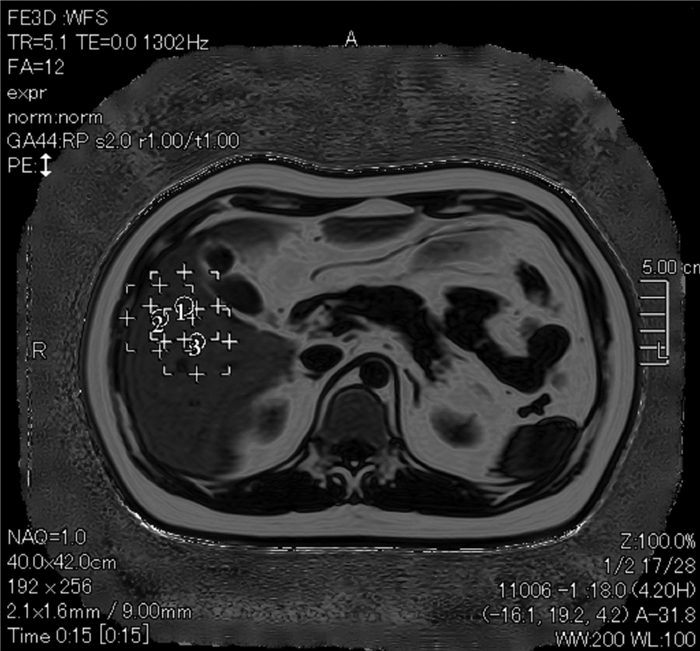

Application of transjugular liver biopsy in the diagnosis and treatment of complicated and severe liver diseases

Hua TIAN, Qiang YU, Shaoli YOU, Sa LYU, Shuhong LIU, Bing ZHU

2021, 37(12): 2874-2877. DOI: 10.3969/j.issn.1001-5256.2021.12.027

Abstract(1173) HTML (235) PDF (2586KB)(79)

Abstract:

Objective  To investigate the application value of transjugular liver biopsy (TJLB) in the diagnosis and treatment of complicated and severe liver diseases.  Methods  A retrospective analysis was performed for the clinical data of 31 patients who underwent TJLB in The Fifth Medical Center of Chinese PLA General Hospital, including indication for puncture, success rate, and final diagnosis.  Results  Among the 31 patients, there were 15 male patients and 16 female patients. Percutaneous liver biopsy was unsuitable for 8 patients with liver failure and disturbances of blood coagulation, 13 with liver cirrhosis and ascites, and 10 with liver cirrhosis and thrombocytopenia (< 50×109/L), which were the indications for TJLB. The success rate of TJLB puncture was 100%, with 2-4 passes for puncture. No serious adverse event was observed. Of all 31 patients, 26 (83.87%) had a definite diagnosis at discharge, among whom there were 5 patients with idiopathic portal hypertension, 9 patients with drug-induced liver failure or liver cirrhosis, 5 patients with autoimmune liver disease, and 7 patients with liver cirrhosis or liver failure due to other causes, and 5 patients had unknown etiology. In addition, 3 patients underwent biopsy to confirm the diagnosis and decision of whether liver transplantation should be performed.  Conclusion  TJLB plays an important role in the diagnosis and treatment of complicated and severe liver diseases and still has certain limitations, and therefore, suitable patients should be selected in clinical practice.